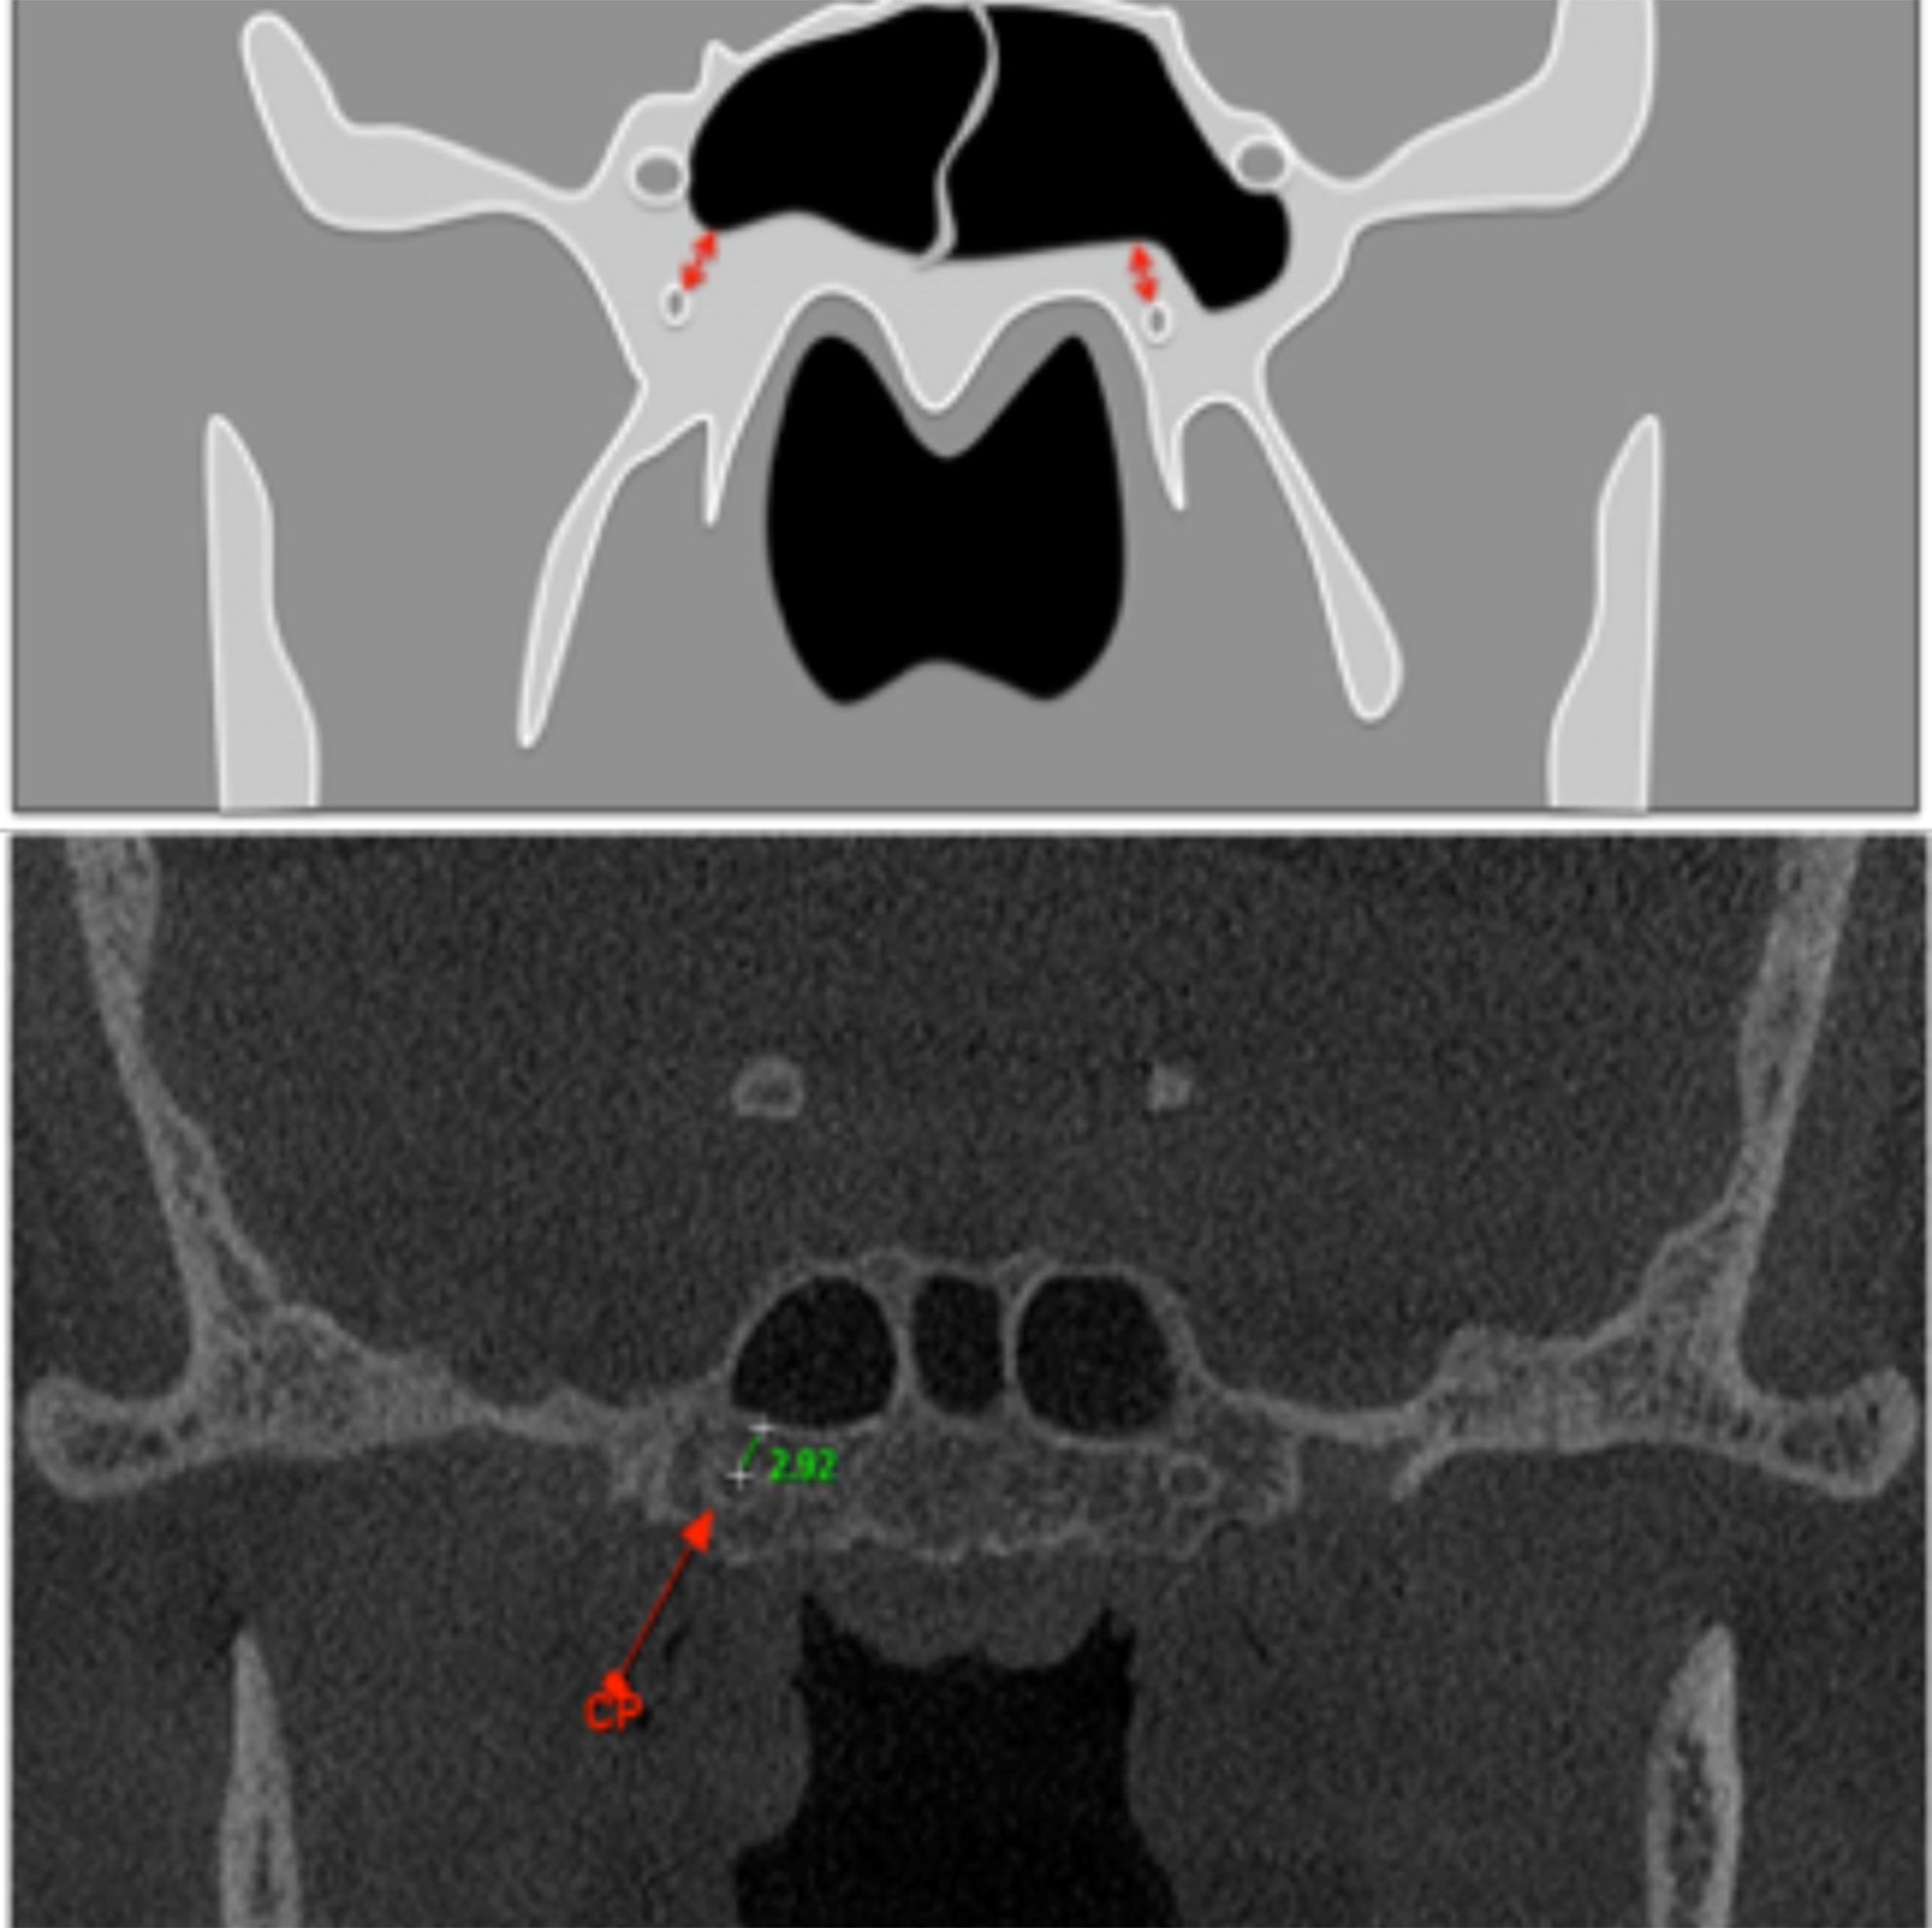

Objective: The aim of this study was to evaluate the pterygoid canal (PC) by Cone Beam Computed Tomography (CBCT), establishing its configuration and proximity with anatomical structures. Material and Methods: We evaluated 398 CBCT exams, all from a public University radiology clinic archive. Four parameters were evaluated: single or double PC, distance between PC and the inferior part of the sphenoid sinus (SS), ratio of PC and SS and the distance between the PC and the foramen rotundum. Results: It was observed that most of the PC of the sample presented simple morphology, the most frequent type of relationship between the PC and the SS on both sides was the close contact with the wall. Among the cases that there were some distances between the PC and the inferior wall of the SS, the mean of this distance did not exceed 3.20 mm, being the left side (3.03 mm) slightly closer than the right (3.20 mm). Finally, the distances between the PC and the corresponding Foramen Rotundum are presented with mean values of 5.87 mm for the right side and 6.31 mm for the left side. Conclusion: CBCT examination is of paramount importance for PC identification; once in the studied sample, the mean values found evidence the close relation between the PC and the SS.